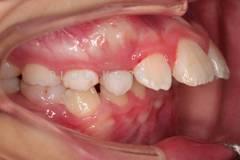

下面這個小患者就存在需早期矯正的問題。通過早期矯正,在不長的時間內(nèi)就達(dá)到極為明顯的療效。她的情況如果等到牙齒替換完畢后再解決,矯治的難度則會非常大。

早期矯正之前